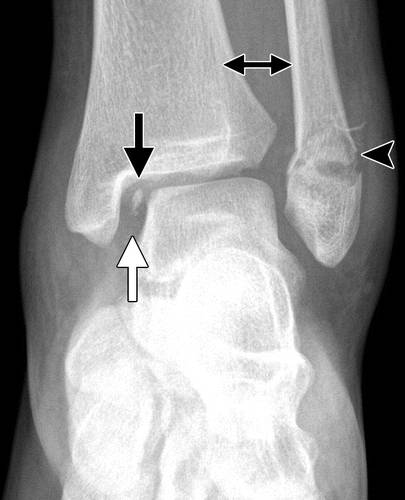

图12a内侧踝关节骨软骨骨折。 AP(a)和斜位(b)踝骨的X线照片显示椎间融合器的移位骨软骨骨折(黑色箭头)。 还注意到倾斜的骨干腓骨骨折(箭头),syndesmotic加宽(双头箭头)和内侧清晰空间加宽(白色箭头b),符合syndesmotic和三角肌韧带复杂损伤的存在。